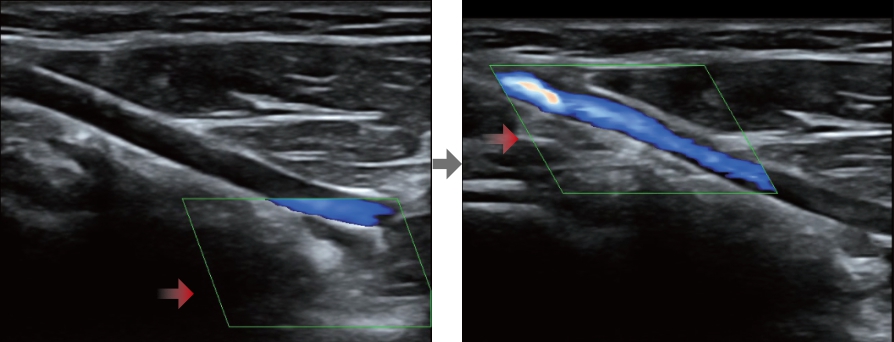

Smart Track

Smart Track proporciona una optimizaciĂłn rĂĄpida e inteligente de imĂĄgenes vasculares con un sencillo manejo de un solo toque. Puede optimizar el espectro de Color, Potencia y PW mediante seguimiento automĂĄtico y reducir pasos que llevan tiempo. Por lo tanto, el flujo de trabajo del examen vascular se simplifica con una Ăłptima visualizaciĂłn.